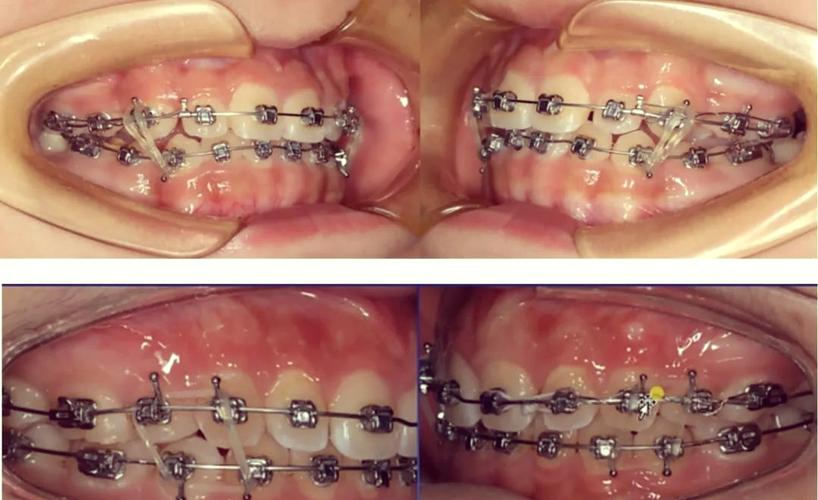

- 弹性牵引:利用弹性材料的回缩力产生牵引,如颌间橡皮筋、链状皮筋、螺旋弹簧等,橡皮筋是最常用的弹性牵引材料,分为轻力(1/4英寸,约50g)、中力(3/16英寸,约100g)、重力(1/8英寸,约200g),需根据牙齿移动阶段选择,链状皮筋用于持续关闭间隙,螺旋弹簧则用于打开间隙或压低牙齿。

- 颌内牵引:同一牙弓内牙齿间的牵引,如将尖牙通过橡皮筋牵引至磨牙远中,以关闭拔牙间隙;或通过“八字形”牵引纠正牙齿旋转。

- 颌间牵引:上下牙弓间的牵引,用于调整上下颌牙齿的咬合关系,常见的有:

- II类牵引:上颌磨牙牵引至下颌磨牙近中,用于矫正上颌前突、下颌后缩(深覆盖);

- III类牵引:下颌磨牙牵引至上颌磨牙近中,用于矫正反颌(地包天)、下颌前突;

- 垂直牵引:如“匣形牵引”,用于纠正深覆颌或开颌。

橡皮筋挂载

严格按照医生标记的牵引方向挂载橡皮筋,例如II类牵引为“上6近中钩→下6远中钩”,避免方向错误导致牙齿移动异常,橡皮筋需无扭曲,拉伸长度为原长的3-4倍(确保力度稳定),每日更换(唾液会导致弹性衰减)。